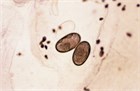

Emergency medicine practitioners routinely see patients with parasitic skin infestation, whether as a chief complaint or as an ancillary finding. This chapter describes the clinical approach to identifying and treating skin infestation by scabies, or human itch mites.

scabies